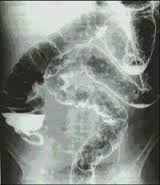

Questo è un esame che si esegue ai raggi X per esaminare le varie problematiche dell’intestino crasso.

Si esegue utilizzando anche un metodo di contrasto che di solito è solfato di bario.